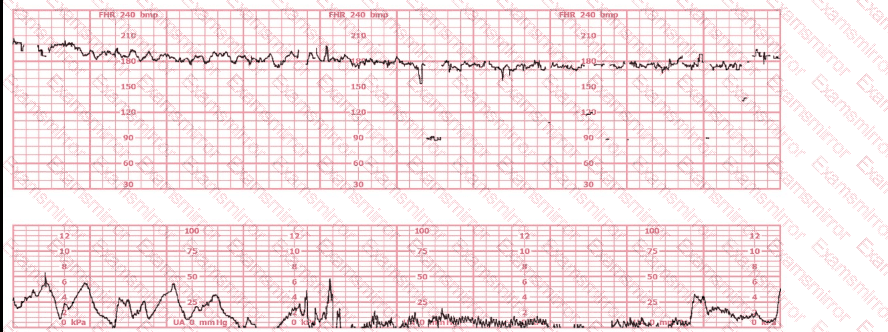

A woman (G1, P0) at 41-weeks gestation presents to OB triage to rule out labor. Her cervical exam is 1 cm/50%/-2. Membranes are intact. She would like to go home if not in labor. Based on this tracing, which represents the last two hours, the best approach is:

This is a tracing of a multiparous woman in the second stage of labor. The vertex is at +3 station. This pattern has continued for the last 20 minutes. She has been pushing for 2½ hours, and oxytocin is infusing at 12 milliunits/minute. Management should include

During the second stage of labor, a period of bradycardia develops. The fetal heart rate baseline variability is moderate. The most likely cause of this bradycardia is:

A 30-year-old woman (G2P0) is experiencing preterm labor at 26-weeks gestation. She is receiving magnesium sulfate for neuroprotection. Her external fetal monitoring tracing over the past 30 minutes is shown. The next step would be to: